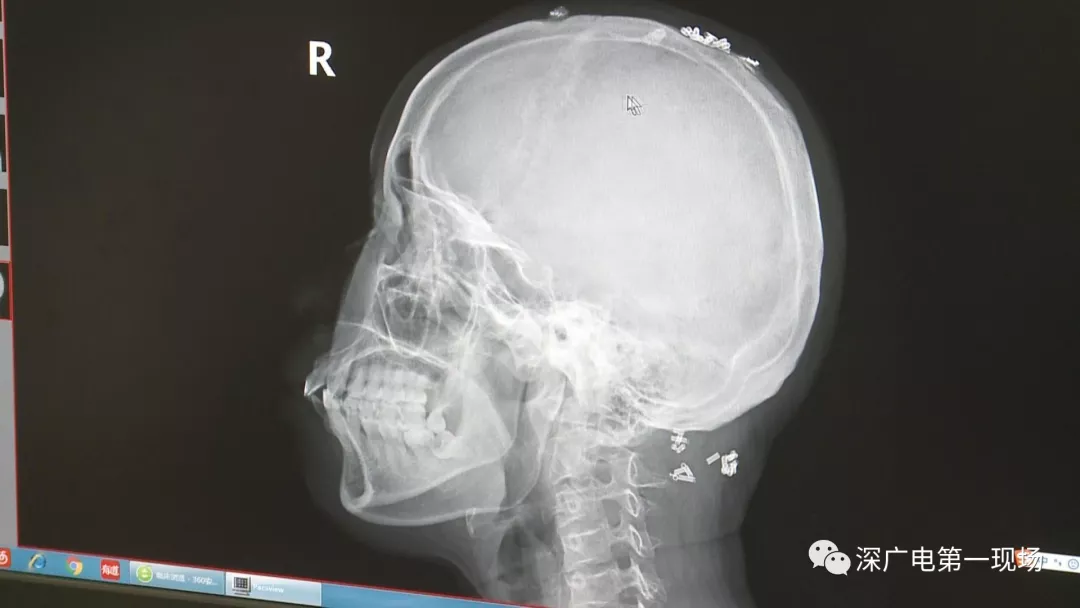

深圳一女子全身被植入彈簧圈,數(shù)量多到驚人!竟是為治這病…

彈簧圈已“寄生”三年

部分形成包塊難以取出

據(jù)了解,這位患者周身的彈簧圈已經(jīng)固定了三年多,因?yàn)榛颊吒杏X治療效果不好,就來深圳求醫(yī)。